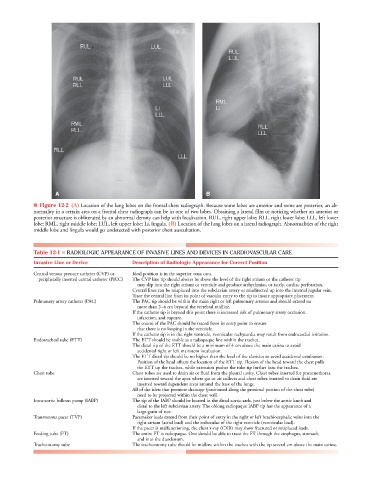

■ Figure 12-2 (A) Location of the lung lobes on the frontal chest radiograph. Because some lobes are anterior and some are posterior, an ab-

normality in a certain area on a frontal chest radiograph can be in one of two lobes. Obtaining a lateral film or noticing whether an anterior or

posterior structure is obliterated by an abnormal density can help with localization. RUL, right upper lobe; RLL, right lower lobe; LLL, left lower

lobe; RML, right middle lobe; LUL, left upper lobe; Li, lingula. (B) Location of the lung lobes on a lateral radiograph. Abnormalities of the right

middle lobe and lingula would go undetected with posterior chest auscultation.